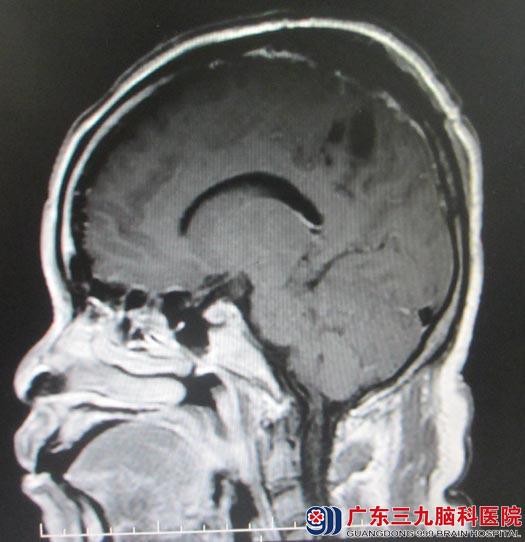

梁阿姨10多天前开始出现持续的头痛,以额部钝痛为主,家属四处求医,吃了很多治疗头痛的药物,但一直不能改善。随即家人带着她来到广东三九脑科医院,头颅MR示“左侧顶部占位,大小约5.6 cm×6cm,考虑大脑凸面的巨大脑膜瘤”。

三天后,鲁明主任主刀在全麻下行“左侧顶部肿瘤切除术”,术中见肿瘤已经侵犯并破坏硬膜,表面血管迂曲杂乱,血供丰富,质地中,边界清楚,小心沿着肿瘤边界分离,电凝离断肿瘤供血动脉,完整切除肿瘤,为了防止肿瘤复发,一并切除受侵犯的硬膜,过程中,周围脑组织保护完好,术中出血少,未输血。术后梁阿姨恢复很好,四肢活动正常,复查头颅MR未见明显肿瘤残留。